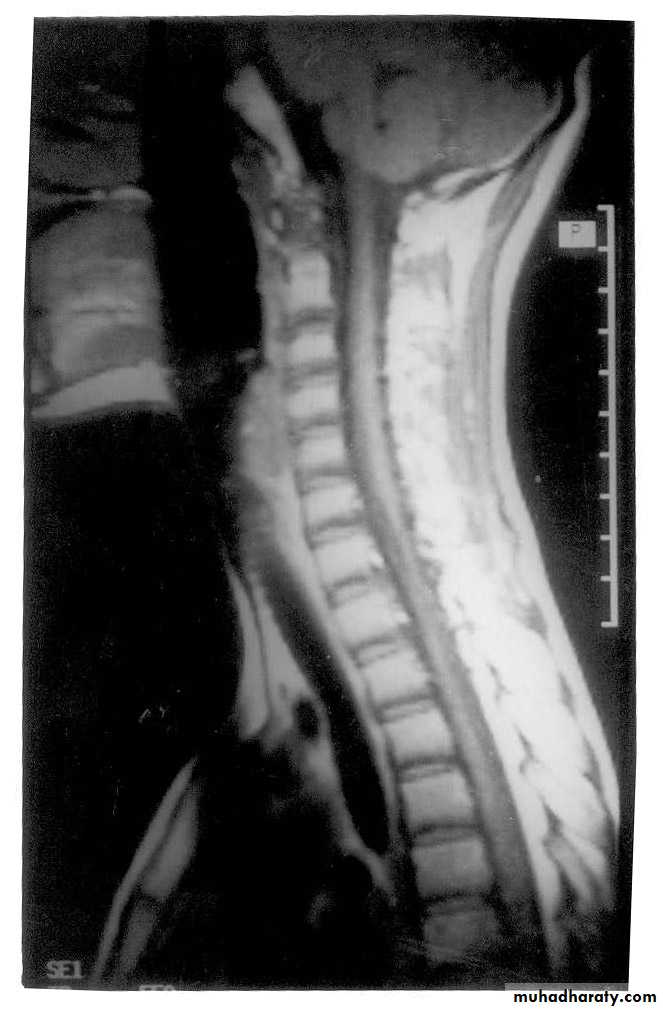

MR imaging